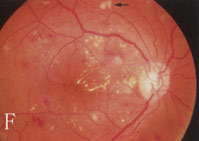

6、其他臟器併發症表現心血管病變如心力衰竭、心肌梗死。神經病變如周圍神經病變。累及自主神經時可出現神經源性膀胱。視網膜病變,糖尿病腎病嚴重時幾乎100%合併視網膜病變,但有嚴重視網膜病變者不一定有明顯的腎臟病變。當糖尿病腎病進展時,視網膜病變常加速惡化。

2.糖尿病視網膜病變和腎臟微血管病二者可同時存在。視網膜病變可繼發於糖尿病腎腎病以後,一般認為網膜病變的發生率高於腎微血管病變。因網膜病變易於觀察,而糖尿病腎腎病難於診斷,所以糖尿病人一旦出現網膜病變,要警惕腎病發生。